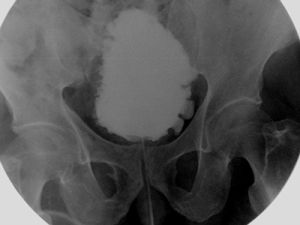

2.檢查①當有會陰部感覺減退,肛門括約肌張力減退或增強時就可確診為神經原性膀胱,但缺乏這些體徵也不能排除神經原性膀胱的可能。②注意有無脊柱裂、脊膜膨出、骶骨發育不良等畸形。③有殘餘尿,但無下尿路機械性梗阻。④電刺激脊髓反射試驗,此法主要試驗膀胱和尿道的脊髓反射弧神經是否完整(即下運動神經元有無病變)以及自大腦皮質至陰部神經核(脊髓中樞)的神經元有無病變(上運動神經元有無病變)。因此,這個試驗即可診斷是滯為神經原性膀胱,又可區分下運動神經元病變(逼尿肌無反射)和上運動神經元病變(逼尿肌反射亢進)。

1.在測量膀胱內壓時,觀察是否有無抑制性收縮;必要地採用站立位測壓、咳嗽、牽拉導尿管等激發方法。如出現無抑制性收縮即屬逼尿肌反射亢進一類。否則,屬逼尿肌無反射一類。

2.冰水試驗用F16導尿管排空膀胱後,快速注入60ml14℃冰水。如系逼尿肌反射亢進膀胱,在數秒鐘內,冰水(如連同導尿管)從尿道中被噴射而出;逼尿肌反射膀胱,冰水自導尿管緩慢漢出。